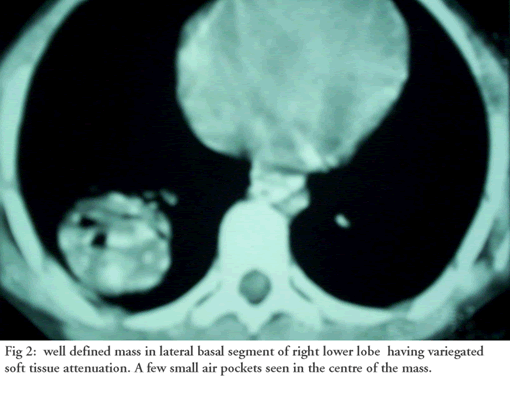

In the evening of July 1, 2005 a ten-year old child was brought to the emergency wing of the Government Medical College, Hospital Jammu in north India with history of two bouts of hemoptysis (each of 200 to 300 mls) on the morning of admission. He initially coughed out dark clotted blood, followed by frothy bright red blood. Examination revealed pallor and bronchial breathing & crepitance in the right infrascapular area. A previous chest x-ray in May 2005 (CXR Figure 1) and contrast enhanced computed tomography chest (CECT, Figure 2) revealed a variegated soft tissue mass in the right lower lobe.

| Figure 1: Rounded radio opacity in right lower lobe. | Figure 2: Well defined mass in right lower lobe having variegated soft tissue attenuation. A few small air pockets seen in the center of the mass. |